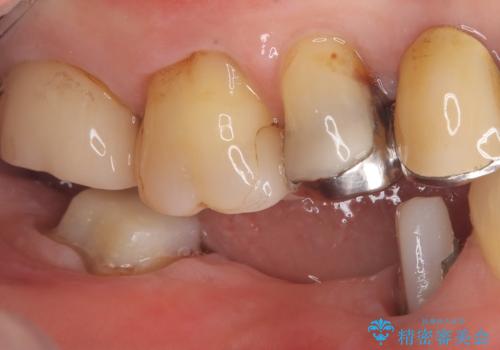

- 主訴:つい先日入れたセラミック(ジルコニア)ブリッジが奥歯部分で割れた。いつも同じ場所で壊れる。これで3度目。

セラミックに比べ、割れづらい金属(ゴールドでのブリッジのやり替えとなりました。

セラミックに比べ、破折リスクの少ない金属を使用したブリッジでのやり替えとなりました。

両支台歯が失活歯のため、どちらかもしくは両方の歯が破折した際、再度ブリッジを除去した治療が必要になるリスクとインプラント治療のご提案もさせていただきましたが、ブリッジでの治療を希望されました。

右下5番は支台歯CR築造を行っています。